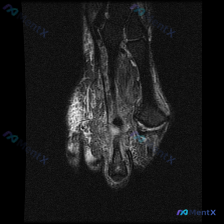

踝关节MRI发现软骨异常?原来是这个典型病变,分享分析思路

看到一份踝关节MRI软骨异常的读片需求,整理一下病例信息和分析思路和大家分享:

本次读片的影像为踝关节MRI-冠状位T1序列,核心问题是评估发现的软骨异常。

- 骨骼结构: 胫骨远端、距骨、腓骨远端结构完整,骨髓信号均匀,无广泛骨髓水肿或肿瘤浸润征象;踝关节对位良好,无明显半脱位

- 关键异常发现: 距骨内侧穹窿边缘可见明确骨性缺损、骨赘样改变,边缘不规则,高度提示存在游离骨块/骨软骨碎片

- 软骨与软骨下骨: 距骨内侧穹窿软骨下骨质信号紊乱,伴明显局灶性骨质缺损,符合骨软骨病变表现

- 韧带软组织: 内侧三角韧带形态可辨认,无明确严重断裂;外侧副韧带无明确完全撕裂征象;关节腔无明显弥漫积液,病灶旁可见局灶软组织信号影,考虑为滑膜反应或与剥脱碎片相关

- 排除恶性征象: 无侵袭性骨破坏、无软组织肿块,不支持恶性病变